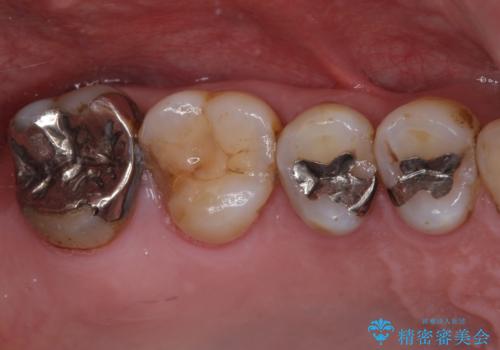

銀歯や虫歯を治したい ゴールドインレーによるむし歯治療